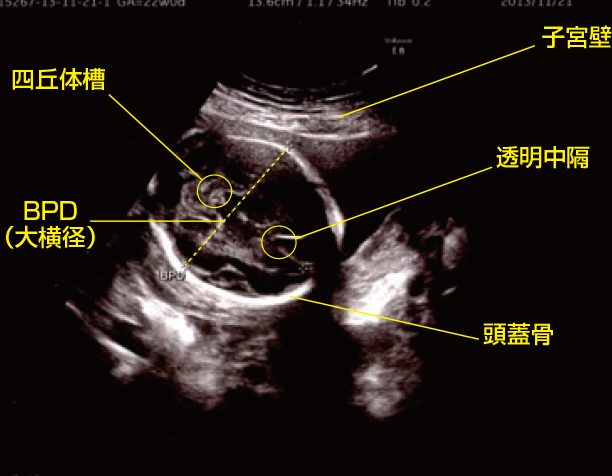

超音波検査は、胎児の成長や健康状態を確認するために広く用いられています。この検査では、音波を使って映像を生成し、胎児の大きさや発達状況を評価します。特に以下のポイントが重要です。

• 頭囲(HC): 胎児の頭部の周囲

• 腹囲(AC): 腹部の周囲

• 大腿骨長(FL): 脚部の骨の長さ

これら3つの測定値から計算される推定体重は、高い精度で胎児体重を把握できる手法として知られています。

超音波検査は、胎児の成長や健康状態を確認するために非常に有用な手段です。この技術を使用することで、私たちは胎児の体重を推定し、その発達過程を理解することができます。超音波検査では、音波によって生成された画像をもとに、さまざまな測定値から胎児の体重が計算されます。

超音波検査で得られるデータ

以下の3つの主要な測定値が、胎児の体重推定において特に重要です:

• 頭囲(HC): 胎児の頭部周囲

• 腹囲(AC): 腹部周囲

• 大腿骨長(FL): 脚部骨長

これらの数値はそれぞれ異なる成長指標を示しており、組み合わせて分析することで、高精度で胎児体重が把握できます。また、この方法は妊娠週数ごとの基準とも照らし合わせることができるため、正確性が増します。